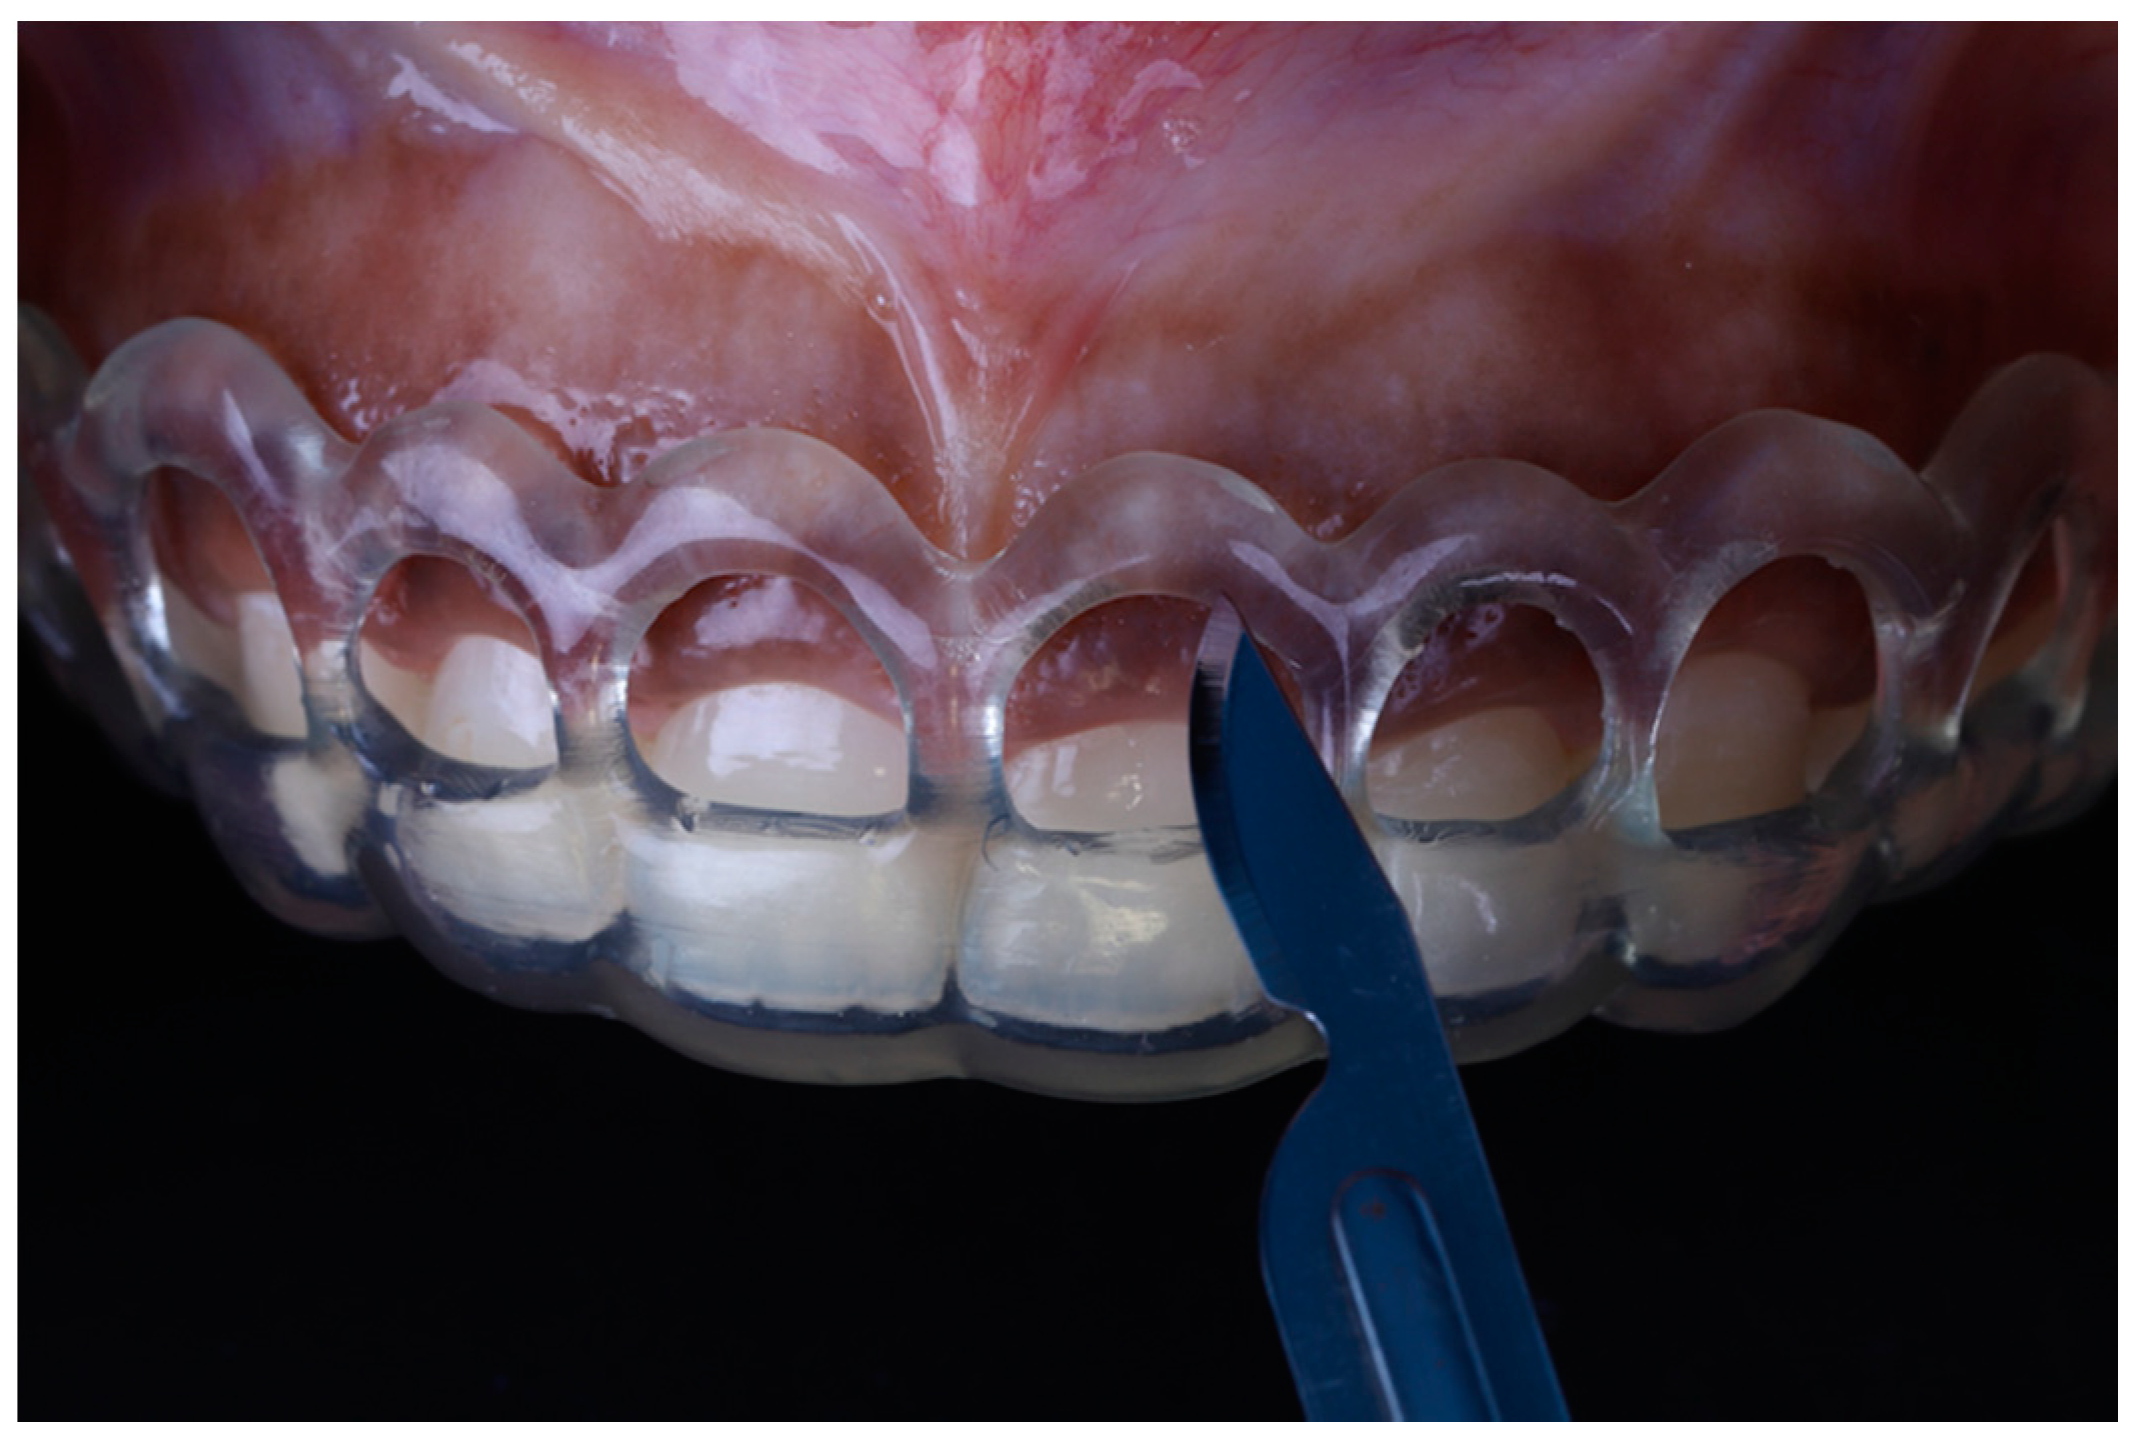

Data was transferred to a three-dimensional printer (Formlabs II; Formlabs Inc., Somerville, MD, USA). The printer used utilizes stereolithography (SLA) technology with Laser Spot size of 140 microns and layer thickness of 25–300 microns. The guide was printed (Figure 4) and then checked to ensure it fits in the mouth of the patient prior to starting the surgery.

Figure 4.

3D-printed surgical guide.

2.2. Surgical Procedure

Local anesthesia (xylocaine with epinephrine 1:100.000) was administered via buccal infiltration. The guide was then placed. Using a 15c blade and following the upper border of the window of the guide, an internal bevel incision was made from right to left first molar teeth (Figure 5). The guide was then removed and a second incision was made in a sulcular fashion. The secondary flap was removed using a Youger-Good curette while visualizing the new crown lengths (Figure 6).

Figure 5.

Surgical incision based on the guide.